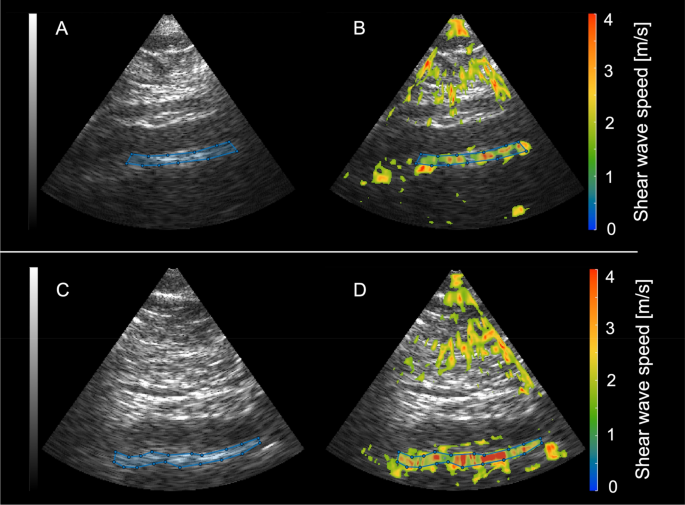

To determine inter-observer variability of SWS measurements, fifteen randomly chosen datasets were anonymized and re-evaluated. Re-evaluation of processed elastograms including placement ROIs along the aortic wall was performed by the initial reader and a second radiologist (TE) with fifteen years of experience in cardiovascular radiology and elastography. The second reader was blinded to the participants’ smoking and health status. Examples of SWS maps are shown in Fig. 1.

Sagittal B-mode images of the abdominal aorta and corresponding elastograms. The top row shows a sagittal B-mode image of the abdominal aorta (A) and the shear wave speed map (measured SWS: 2.77 m/s) (B) of a healthy non-smoking volunteer. The bottom row shows the corresponding B-mode image (C) and SWS map (measured SWS: 3.03 m/s) (D) of an age-matched smoker.